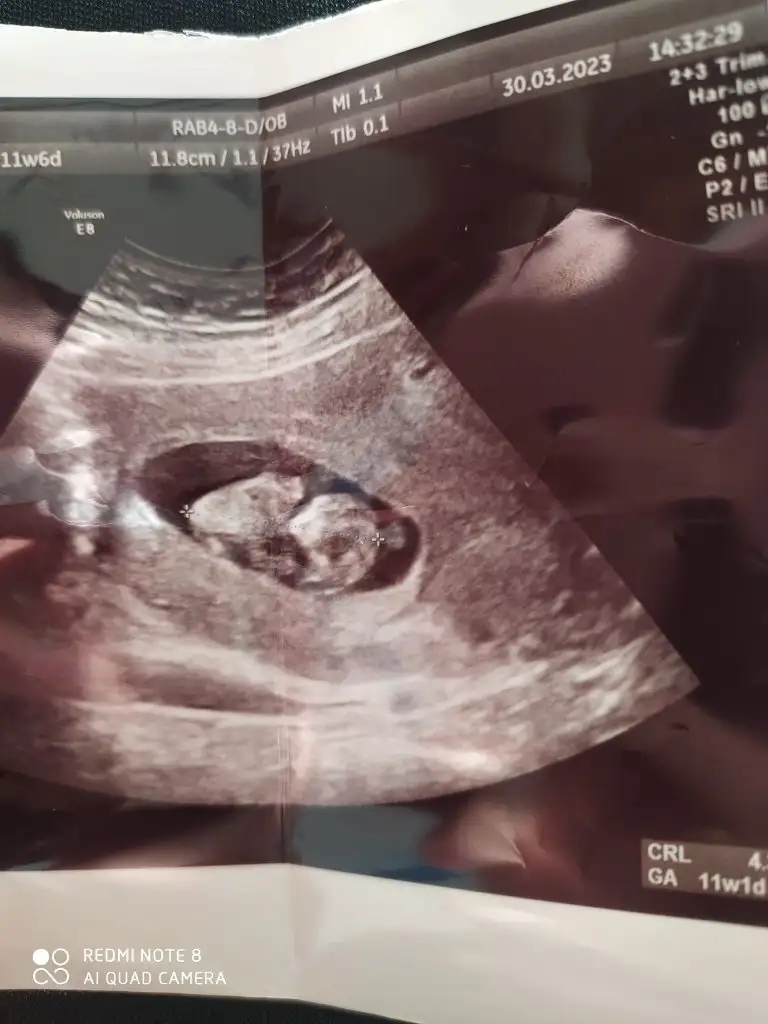

Merhaba kaçıncı hafta ultrasonundan anlıyorsunuz acaba 6+5 ve 9+4 ultrasonlarından anlarmısınızKız bu

Arkası dönük yaabize de bakar mısınızzzzz:) C catloverrrr

12 olsun biMerhaba kaçıncı hafta ultrasonundan anlıyorsunuz acaba 6+5 ve 9+4 ultrasonlarından anlarmısınız

Kesin kız şüphem yokbenim bebeğimle aynıı görünüyor benimki büyüdü artık netleşti